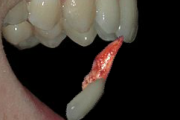

krooni murd paljastunud pulbiga (Mitsuhiro Tsukiboshi,DDS)